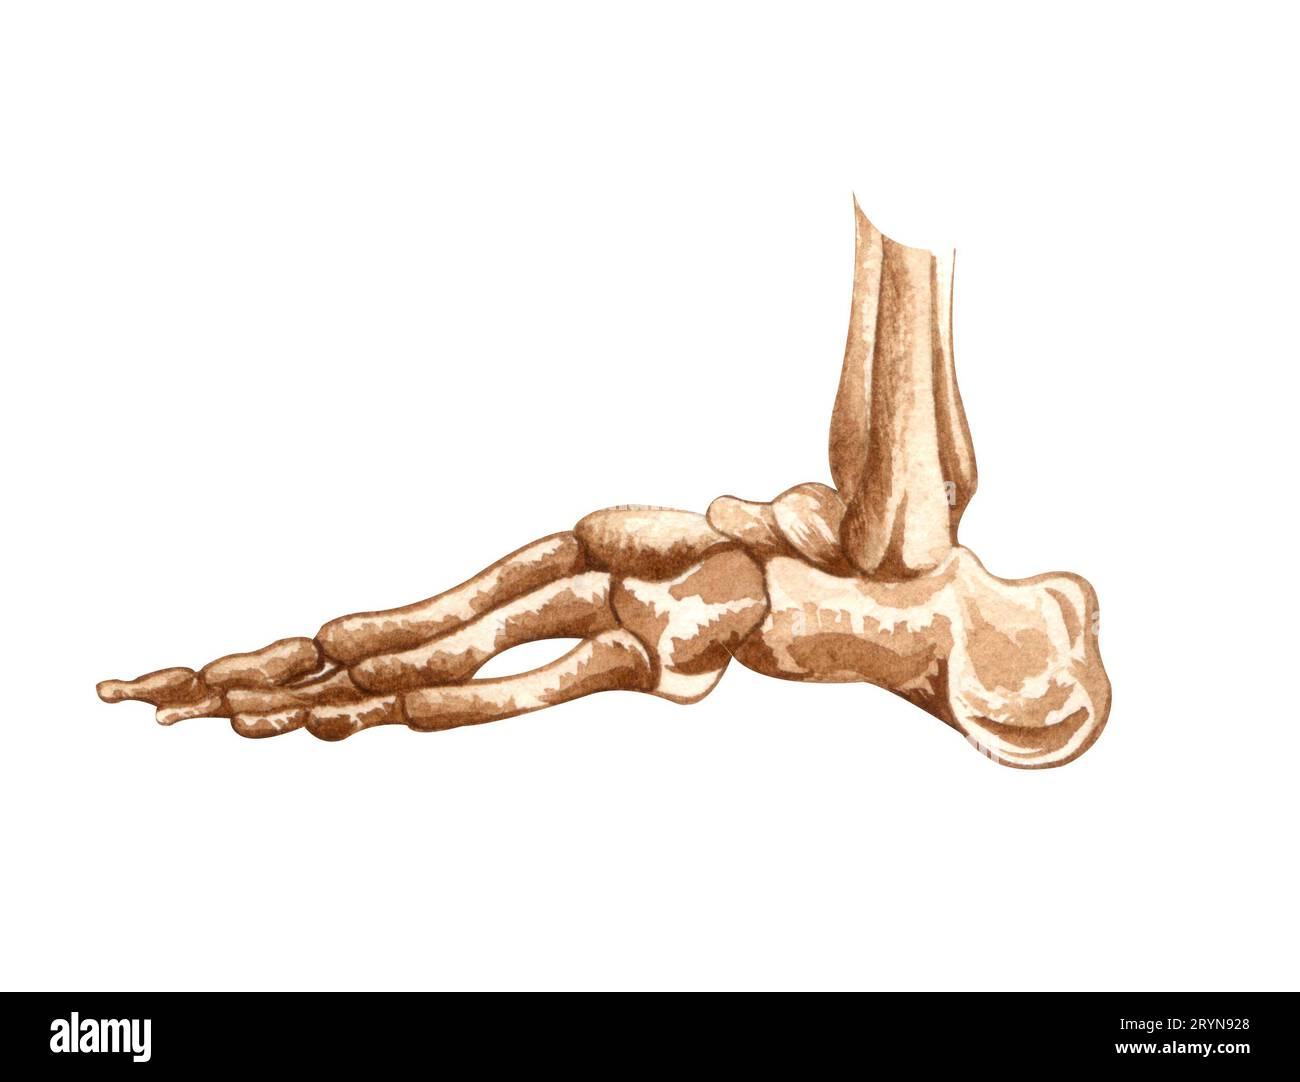

RF2RYN928–Structure du squelette humain aquarelle. OS du pied. Anatomie et médecine. Illustration orthopédique